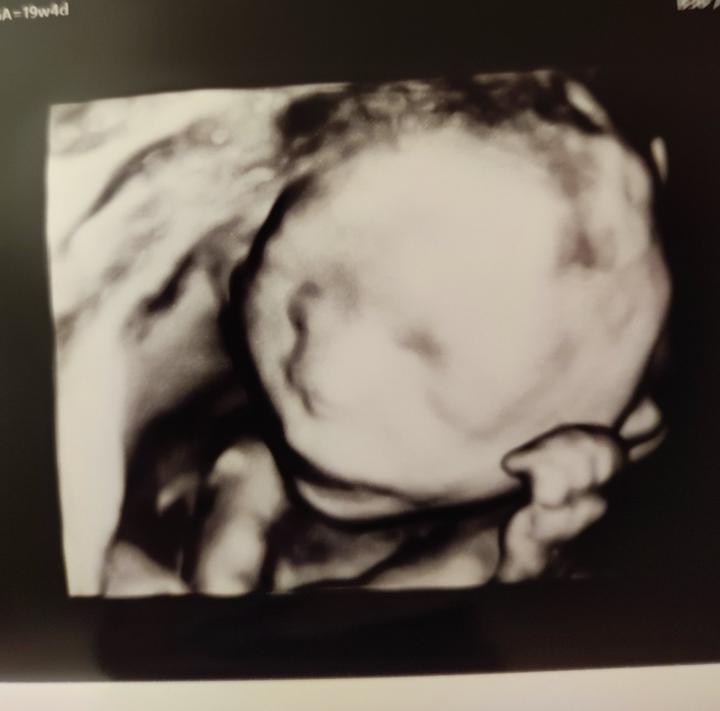

Kedy je citit pohyby babatka cez brusko aj pre inu osobu? Toto si uz fakt nepamatam, deti sa stale pytaju, kedy budu aj oni citit maleho...ja ho uz citim dost dlho, koncime 18.tyzden... Este mesiac? Ci dlhsie? Nevedia sa dockat...

Koncime 16.tyzden a to male v brusku pol dna v pohybe, ze vazne zacinam uvazovat, ze sa nam narodi hypermobilna verzia mladsieho syna 😂 Boh nam pomahaj, ked to fakt tak bude 😅

Po dnesku mame jasno😂Nase duhove babatko bude chlapcek🥰🥰 A hlavne podla rozsirenej genetiky uplne zdravy👍👍